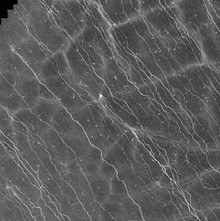

Die korneale konfokale Mikroskopie (CCM) ist ein weiteres innovatives Untersuchungsverfahren, welches für Diabetiker in ersten klinischen Studien getestet wurde. Mit dieser Methode kann u.a. das subbasale Nervenfasergeflecht der Hornhaut dargestellt werden (Abb. 3), was für die Diagnostik der diabetischen peripheren Neuropathie und anderer Polyneuropathie-Formen von großem Interesse ist. Das Verfahren ist nicht-invasiv und ermöglicht durch digitale Überlagerung von Einzelbildern auch die Bewertung größerer Gewebeareale.

Mittels einer geeigneten Software können so Dichte, Länge und die Art der Verzweigung innerhalb des Nervenplexus analysiert werden. Erste Studien deuten darauf hin, dass mit der kornealen konfokalen Mikroskopie eine diabetische Polyneuropathie vor dem Auftreten von elektrophysiologischen oder klinischen Veränderungen erfasst werden kann (Ziegler et al. 2014).